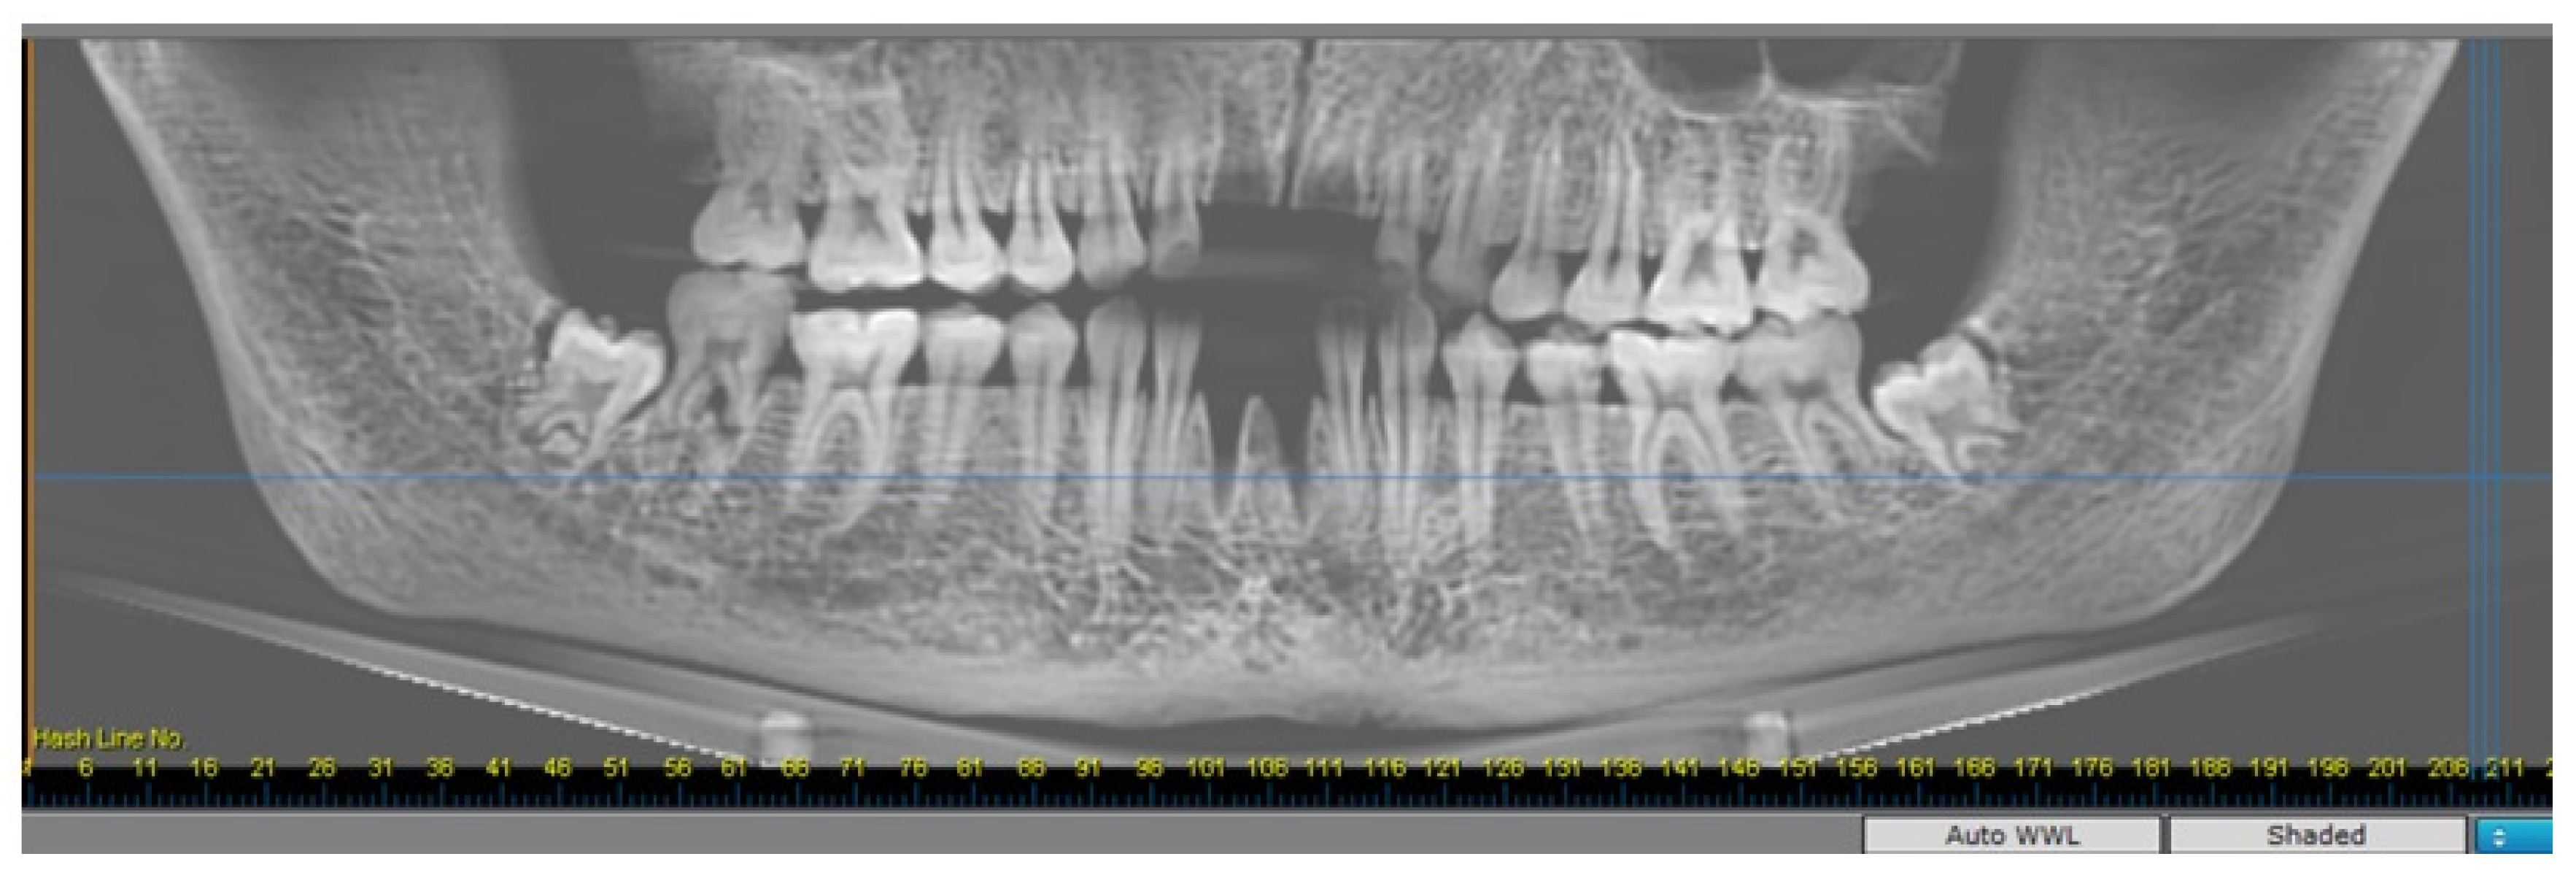

2.2. Radiomorphometric Assessments